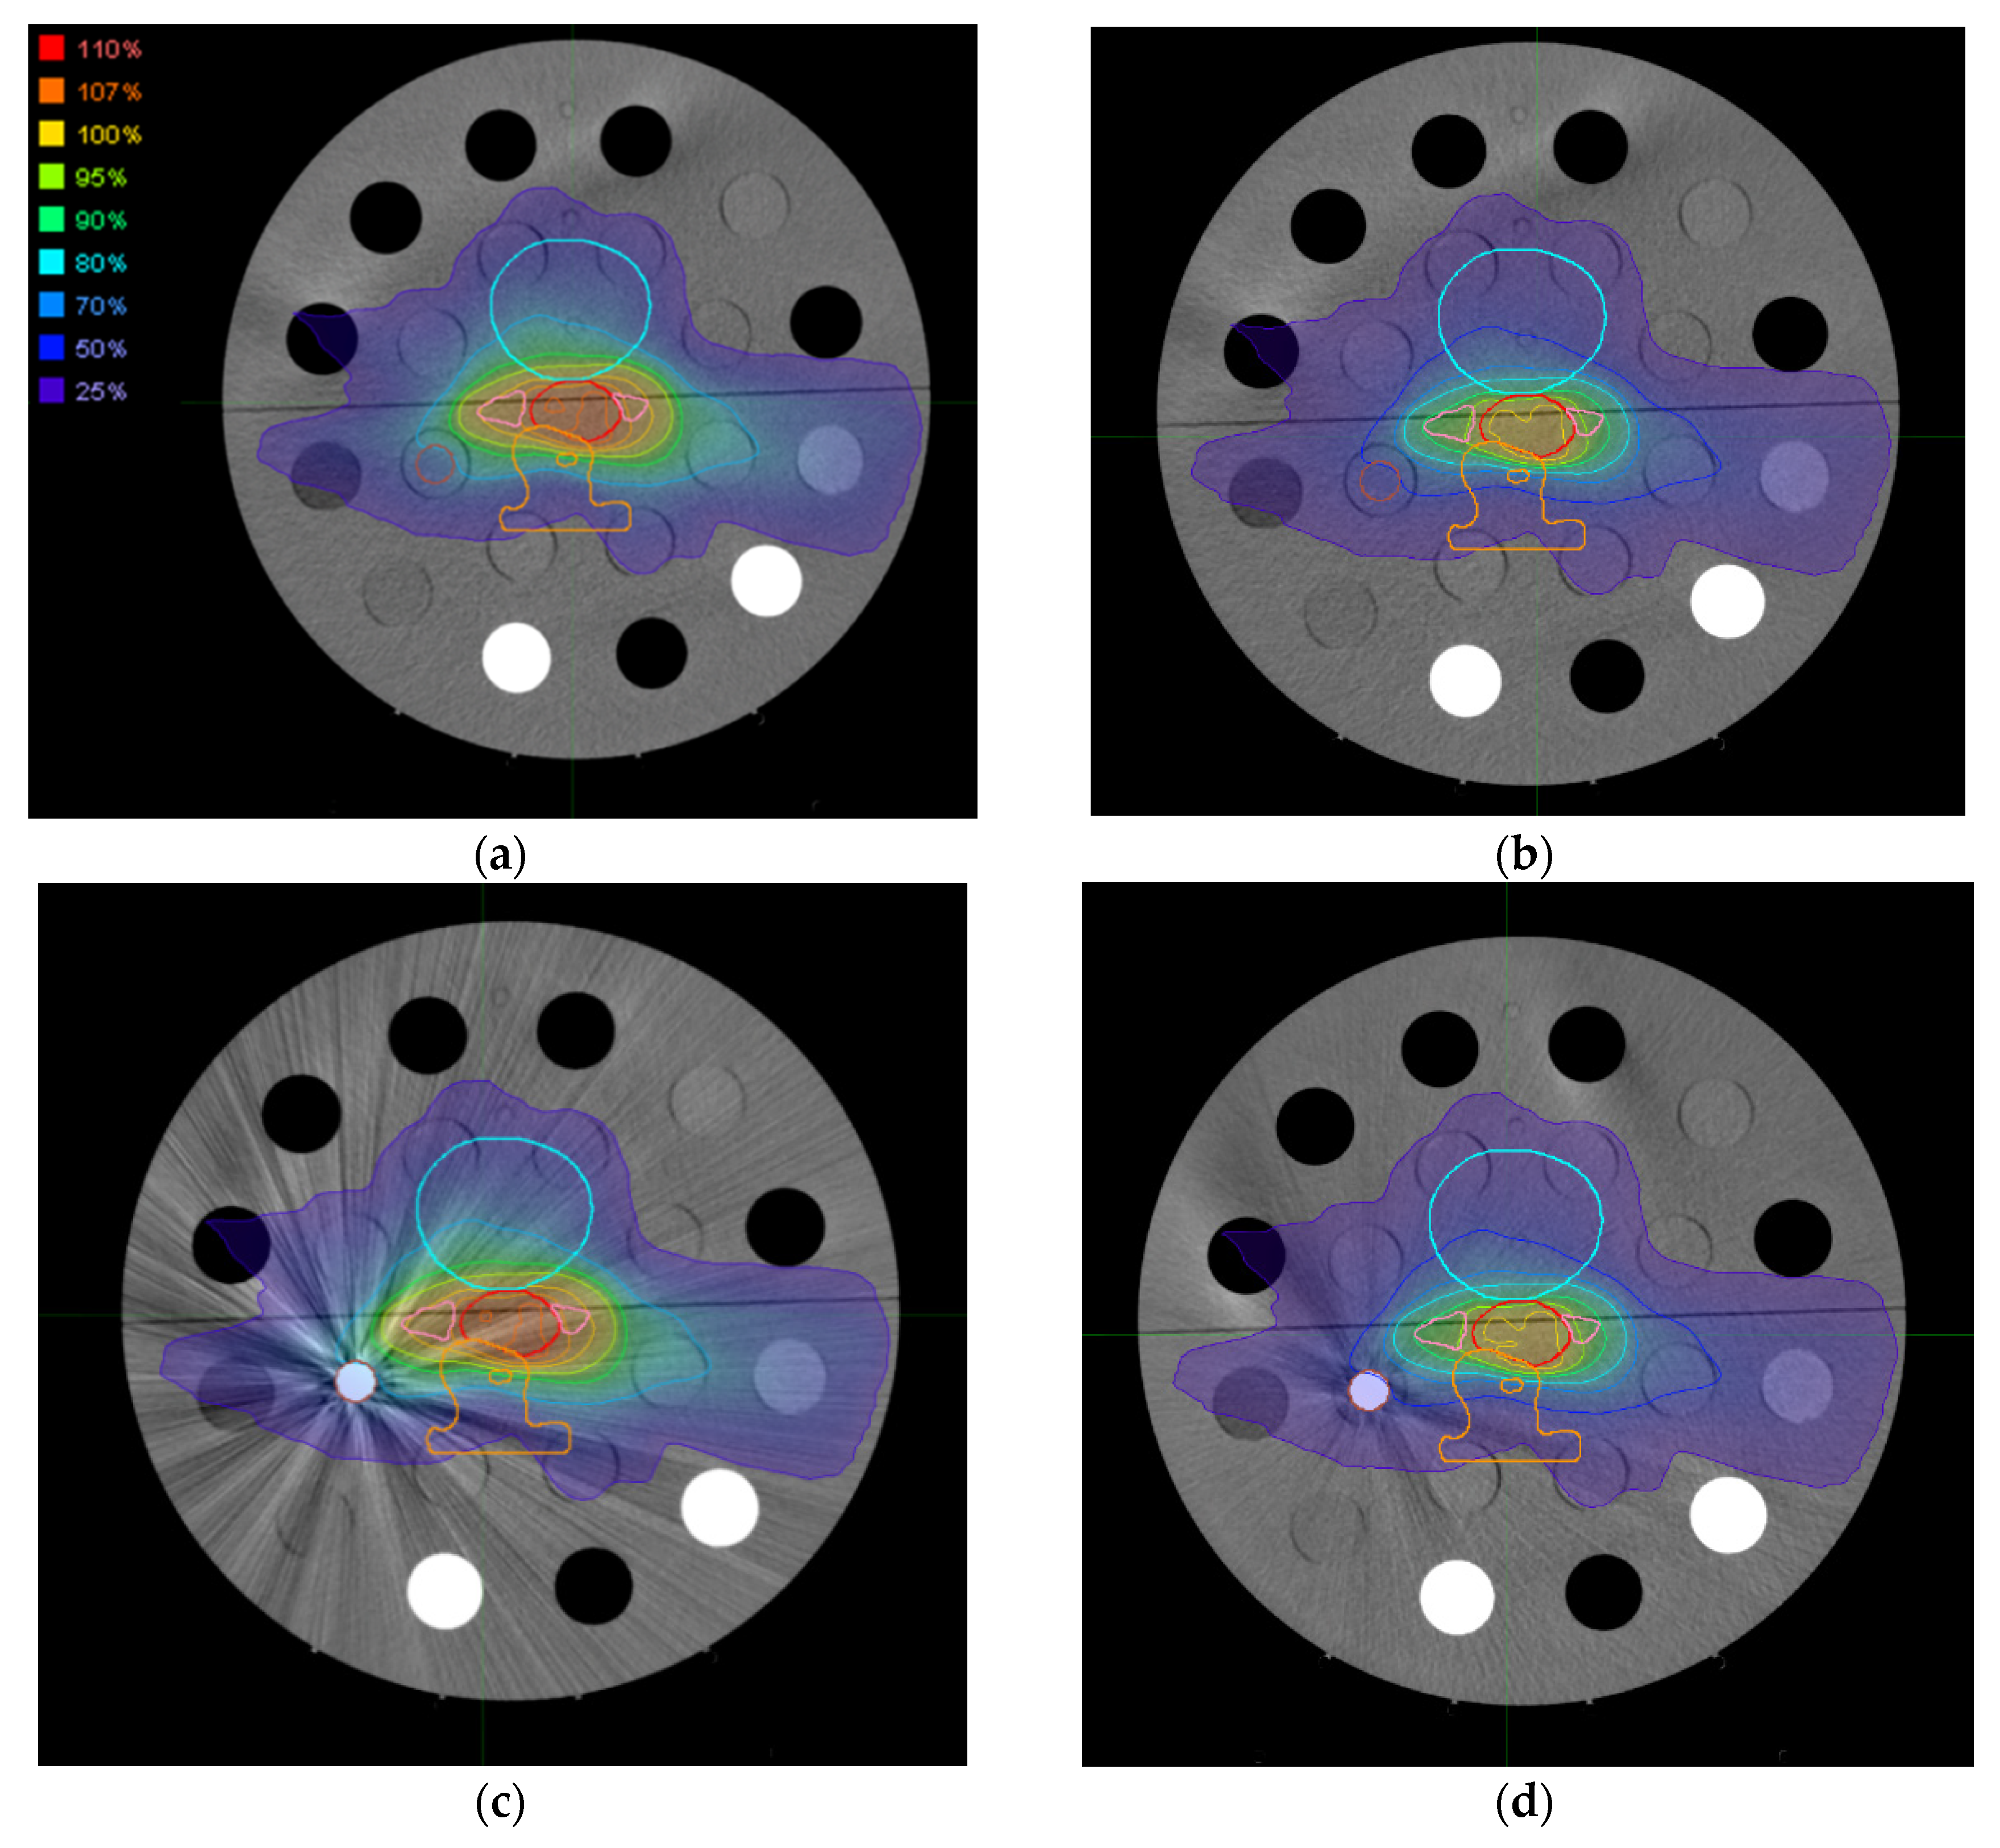

3.3. Dose Distributions